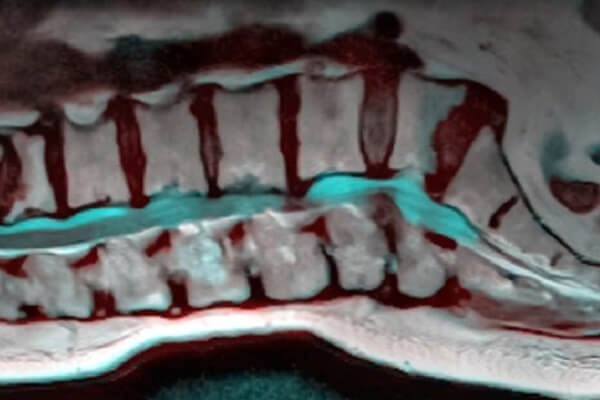

آرتروز کمر یا ستون فقرات

آرتروز کمر باعث ایجاد درد در ستون فقرات یا کمر می شود.

اگر پشت درد دارید ممکن است آرتروز ستون فقرات داشته باشید. این بیماری بر مفاصل واقع در پشت کمر و باسن اثر می گذارد.

ترومای ستون فقرات و افزایش سن هر دو عامل بالقوه در بروز آرتروز ستون فقرات هستند.